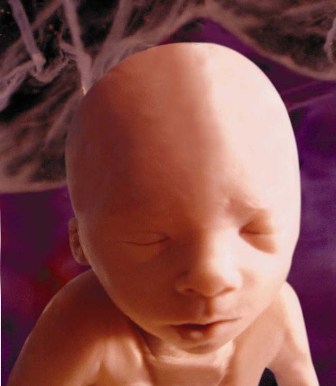

Gebeliğin en kritik dönemi artık sona ermiştir. Bu haftada beyin hızla büyümesini sürdürmektedir ve fetus'un boyunun yarısını kafa oluşturmaktadır. Başı ile gövdesi hemen hemen aynı boyuttadır. Organ gelişimi büyük ölçüde tamamlanmıştır. Fetus'un gözleri kapalıdır ve bu göz kapaklarının altında iris tabakası olgunlaşmasına devem etmektedir. Böbreklerde idrar üretimi başladığından içinde yüzdüğü amniyon sıvısının da miktarı artmaya başlar ve bu haftada yaklaşık 50 ml olur. Bebek tekmeler atmasına rağmen anne henüz hissedemez. Boy: 7 cm. Ağırlık 8gr.

Bebeğin yüzü insan görünümündedir, ağız içinde ise üst damak birleşmeye başlamıştır. Yüz derisi içinde kıl kökleri belirmeye başlar. Ellerde ve ayaklarda tırnaklar uzamaya başlar. Bu haftada bebeğin bütün iç organları çalışır durumdadır. Çişini yapabilir. Tırnaklar gelişir. Bu haftadan sonra bebeğinizin ilaçlardan ve zararlı etkenlerden zarar görme olasılığı azalır. Cinsel organları cinsiyetini ortaya koyacak kadar gelişmiştir. Ancak ultrasonda bu ayrımı yapmak mümkün olabilir, ancak yanılma payı yüksektir. Boy:8 cm, Ağırlık: 18 gr.

Baş-popo uzunluğu 6-8 cm kadardır. Baş vücuttan büyük veya vücut kadardır. Gözler birbirine daha yakın, görünüm gittikçe daha çok insana benzemektedir. Barsaklar karin içerisindeki normal yerlerine geçer. El ve ayak parmakları tamamen oluşmuş, eklemler çalışmaktadır. Dış cinsel organlar artık görünür hale gelmiştir.

Bebeğin baş popo uzunluğu 8-10 cm, ağırlığı yaklaşık 25 gr'dır. Kulaklar başın arkasından daha öne ve yanlara doğru gelir. Çene belirginleşir. Bebeğiniz dışarıdan gelen uyarılara (rahime ultrason probu ile basınç yapıldığında) kıvrılıp doğrularak yer değiştirir. Bebeğiniz artık yutkunmakta ve çişini yapmaktadır.